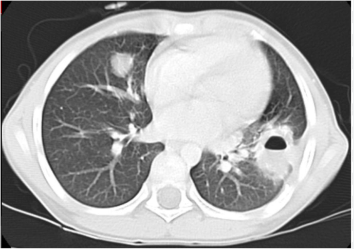

Biểu hiện chính của bệnh được phát hiện ngẫu nhiên trên các hình ảnh chụp X-quang. Tuy nhiên, bệnh nhân có thể trải qua các triệu chứng như ho, ho ra máu, đau ngực hoặc tràn khí màng phổi. Các hình ảnh chụp X-quang của bệnh nang sán phổi khác nhau giữa E. granulosus và E. multilocularis. Bệnh nang sán do E. granulosus,khi các nang chưa bị vỡ, sẽ tạo ra các nốt hoặc khối có bờ mịn và không bị vôi hóa. Ngược lại, loài E. multilocularis gây ra bệnh Echinococcosis phế nang (Alveolar Echinococcosis) và trên hình ảnh chụp X-quang hoặc CT scan, bệnh này xuất hiện dưới dạng các nốt hoặc khối có hình dạng tạo thùy và có sự vôi hóa.

Các đặc điểm chính của nang sán trên hình ảnh X-quang bao gồm: dấu meniscus, dấu bán nguyệt, dấu Cumbo, dấu vỏ hành tây, dấu hoa súng và dấu khối trong khoang. Một trong những dấu hiệu kinh điển trên hình ảnh X-quang của nang sán là một vùng sáng tròn rõ ràng trong phổi, có hoặc không có sự vôi hóa(Hình 6). Bệnh nang sán phổi có thể bị nhiễm trùng thứ phát và trên hình ảnh X-quang ngực có thể xuất hiện u nang và mức dịch khí (Hình 7).

Hình 6.Chụp X-quang phổi thông thường cho thấy có  một vùng sáng tròn rõ ràngnằm ở vùng thấp bên trái của phổi.

|   Hình 7.Hình ảnhX-quang ngực nghiêng cho thấy mức dịch khí bên trong một nang sán đã tồn tại từ trước gợi ý  nhiễm trùng chồng lấn.